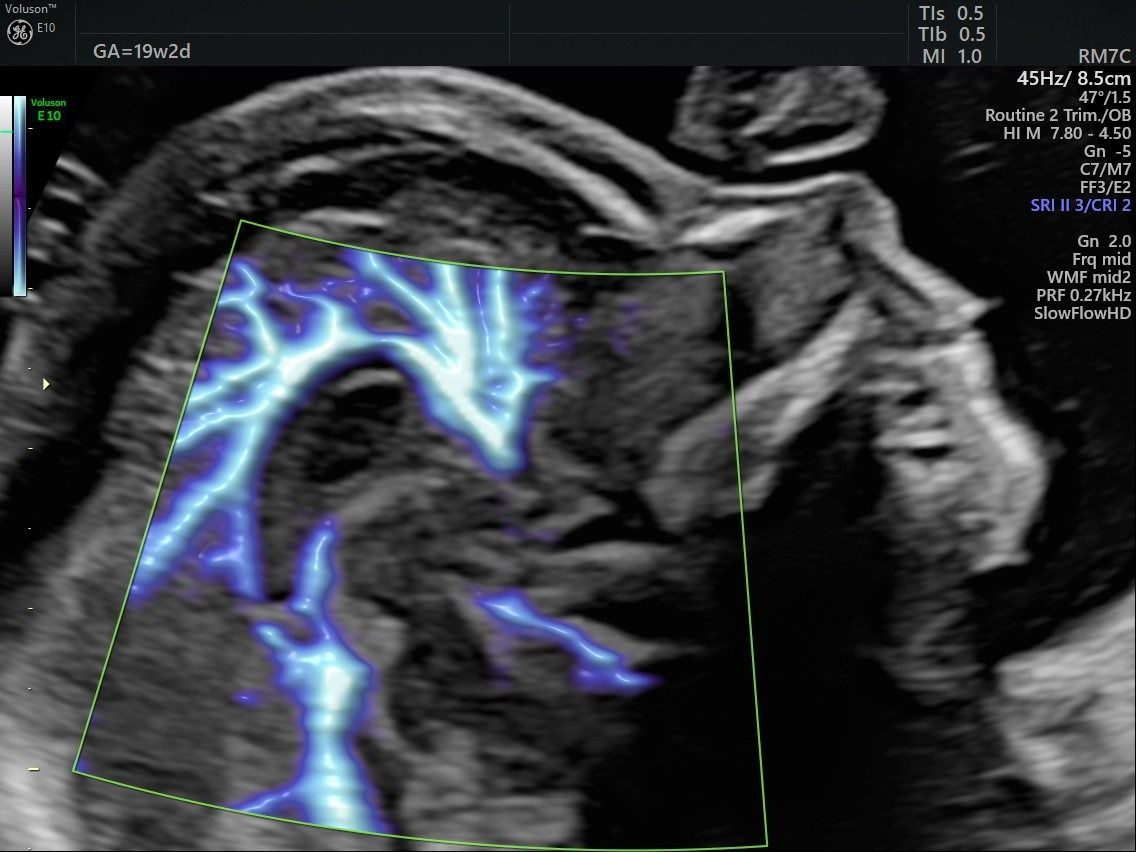

Eseguo in particolare ecografie ostetriche e ginecologiche anche in 3D e 4D per meglio identificare la problematica, offrire diagnosi precise ed un trattamento mirato e personalizzato.

• Arcispedale Santa Maria Nuova - IRCSS Reggio Emilia ecografia ostetrica terzo trimestre  •

Dr. Andrea Musarò

Grazie Laura, gentilissima!

Felice di avervi incontrato.

Un saluto.